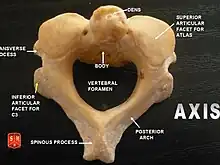

The axis' defining feature is its strong odontoid process (bony protrusion) known as the dens, which rises dorsally from the rest of the bone.

Dens

The dens, also called the odontoid process, or the peg, is the most pronounced projecting feature of the axis. The dens exhibits a slight constriction where it joins the main body of the vertebra. The condition where the dens is separated from the body of the axis is called os odontoideum and may cause nerve and circulation compression syndrome.[1] On its anterior surface is an oval or nearly circular facet for articulation with that on the anterior arch of the atlas. On the back of the neck, and frequently extending on to its lateral surfaces, is a shallow groove for the transverse atlantal ligament which retains the process in position. The apex is pointed and gives attachment to the apical odontoid ligament. Below the apex, the process is somewhat enlarged and presents on either side a rough impression for the attachment of the alar ligament; these ligaments connect the process to the occipital bone.

The pedicles are broad and strong, especially in the front, where they coalesce with the sides of the body and the root of the odontoid process. They are covered above by the superior articular surfaces.

The laminae are thick and strong. They play a large role in the stability of the cervical spine alongside the laminae of C7.[2]

The vertebral foramen is large, but smaller than the atlas.

The transverse processes are very small, and each ends in a single tubercle. Each process is perforated by the transverse foramen, which is directed obliquely upward and laterally.

The superior articular surfaces are round, slightly convex, directed upward and laterally, and are supported on the body, pedicles, and transverse processes.

The inferior articular surfaces have the same direction as those of the other cervical vertebrae.

The spinous process is large, very strong, deeply channelled on its under surface, and presents a bifurcated extremity.